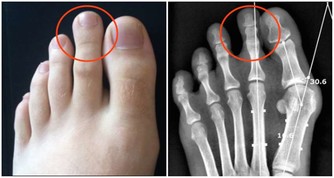

2. 有胃病的人

有胃部疾病,包括胃炎、胃潰瘍的人,也需要禁用阿司匹林,因為阿司匹林可能會導致胃出血。研究發現,如果每天服用10毫克左右的阿司匹林,將會對胃壁造成損傷。而胃壁是保護胃部的,這就很容易出現胃潰瘍。所以服用阿司匹林對於有胃病的人來說,是比較危險的。